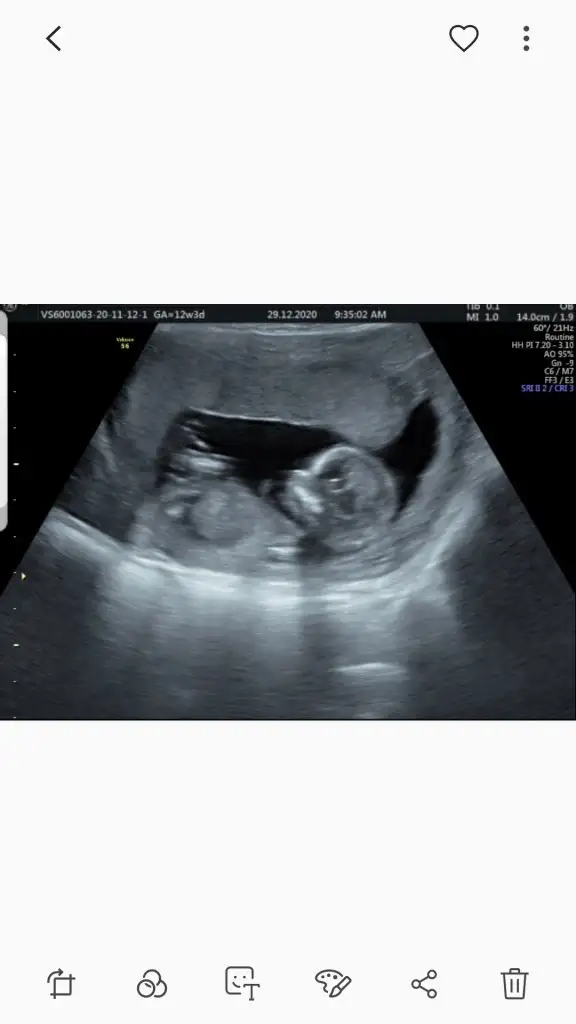

dr soylemeden siz gorun genital nub teorisi ( bebegin cinsiyeti)

Sanırım bunlarda net değil..